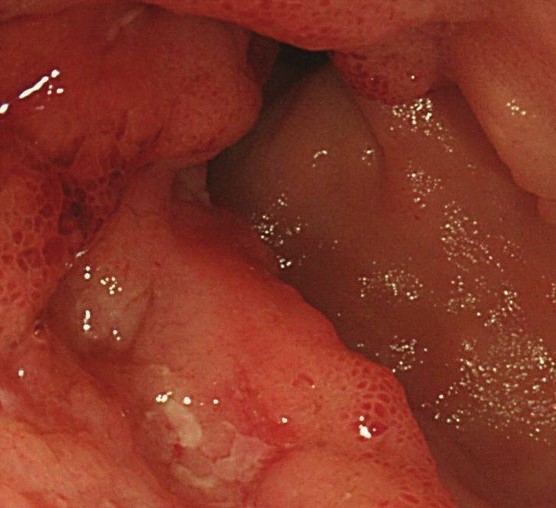

The adenocarcinoma is clearly seen nearby the ileal pouch anal anastomosis (Courtesy Dr. V. Penopoulos)

Endoscopic view of ileal pouch - anal anastomosis 3 years before the development of adenocarcinoma (Courtesy Dr. V. Penopoulos)